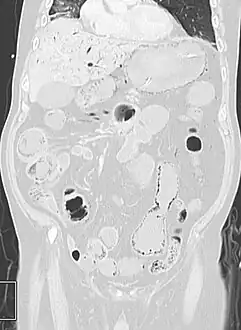

Pneumatosis intestinalis in the coronal computed tomography in lung window. It can be seen next to gas entrapment in the bowel wall and gas in the stomach wall and in numerous vessels, including the portal vein into the liver.